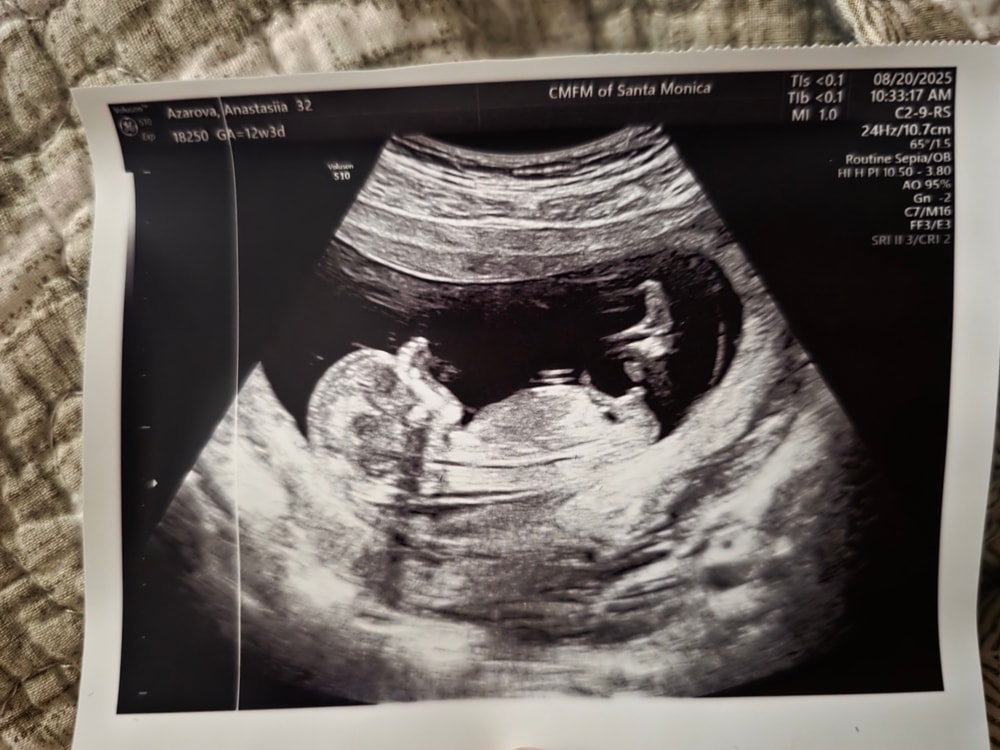

В 12 недель половые органы плода не имеют выраженной половой дифференциации, поэтому ценность « думания» комментаторов равна ценности подбрасывания монетки. Подождите 2 недели.

anasta, ну да, это вид снизу на попку и бедра. Видно торчащий половой признак вашего сына) У моего так же торчал в 11+5, врач УЗИ сразу сказала - мальчик. Но некоторые тут на форуме в истерике бились, утверждая, что НИКТО КРОМЕ НИХ НИЧЕГО НЕ ПОНИМАЕТ, там у всех все одинаковое на этом сроке)) собственно тут в комментах тоже есть эти люди

Поле Имя, ну все тут эксперты узи, конечно 😀 Класс. Спасибо за ответ. Видимо и правда сын🤩